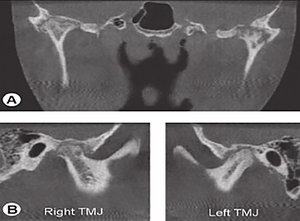

Cone beam CT, introduced in the 1990s, is a modality that can be available in a dental practice. The main advantage of cone beam CT, compared to CT, is the lower radiation dose to the patient. The spatial resolution of cone beam CT is also higher than that of conventional CT.9 (Fig. 4)

FIG 4 Cone beam CT of the TMJ.